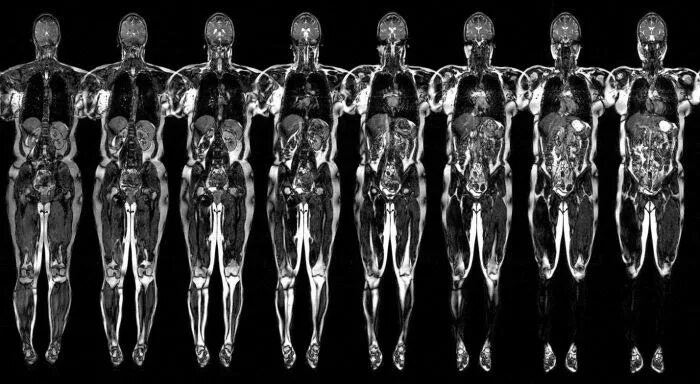

Мрт полностью